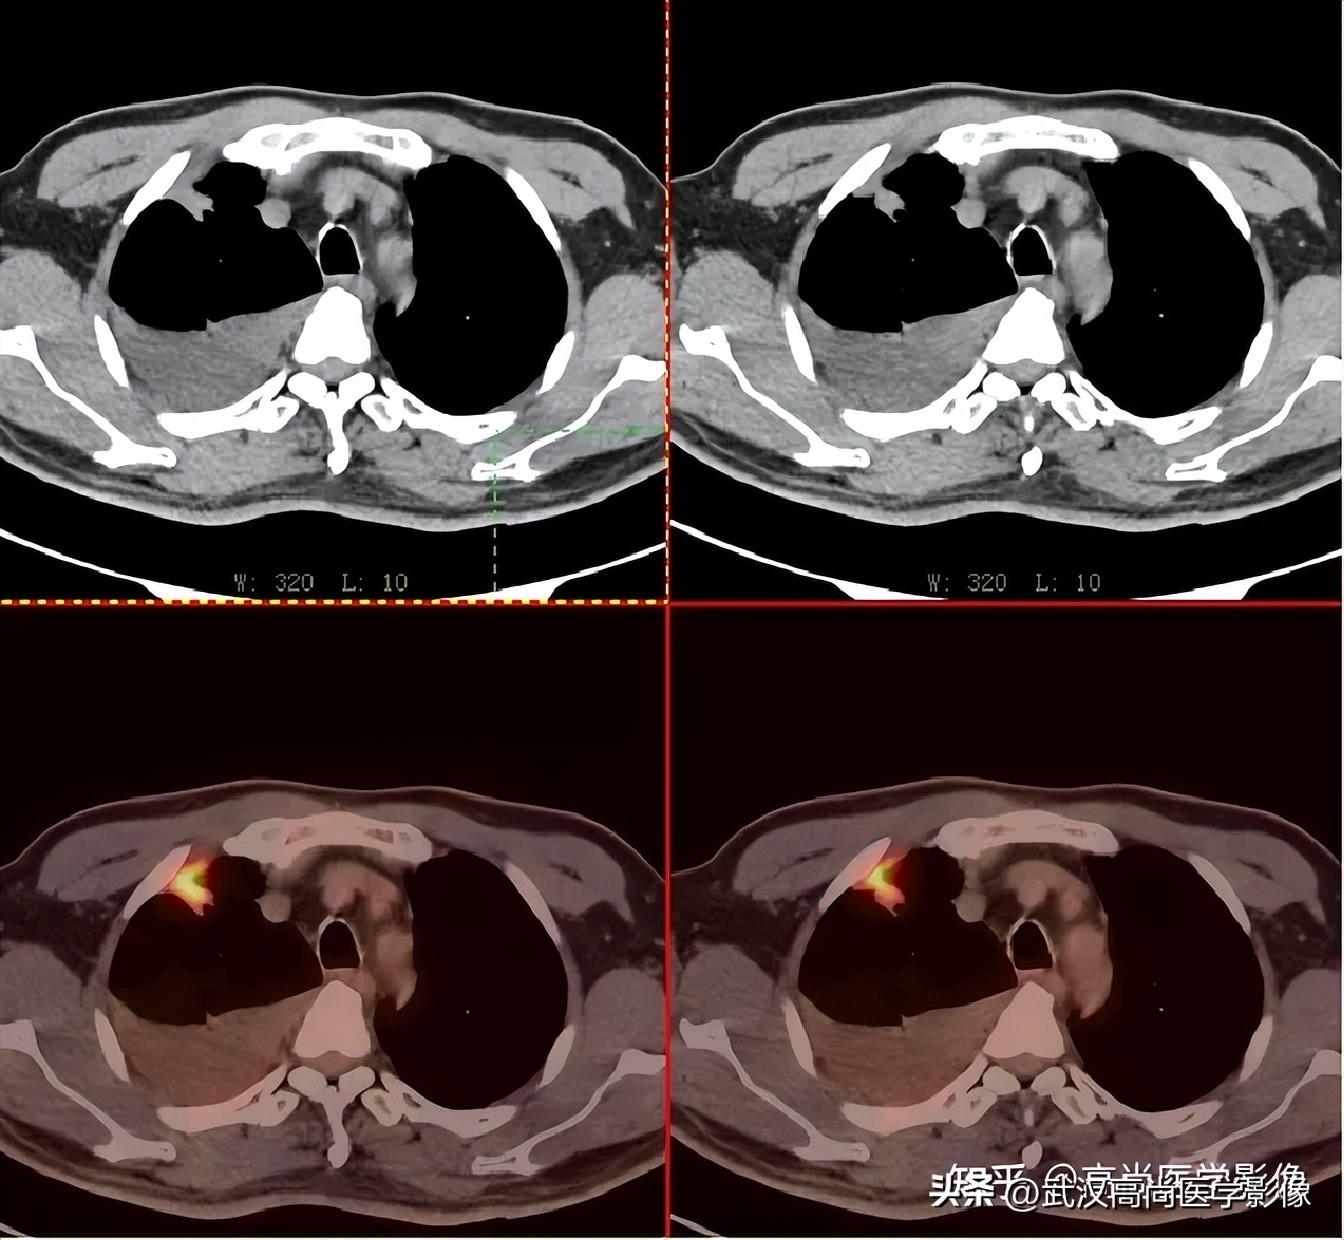

全身PET/CT

影像表现:

右肺上叶尖段胸膜下见一实性结节,范围约1.6cm×1.3cm,病灶紧贴邻近胸膜,伴牵拉增厚,FDG高摄取,SUVmax为7.5。

恶性CT征象:

结节边缘不光整,分叶、长短不一的毛刺,邻近胸膜牵拉明显。

右侧胸膜区多发条片状代谢增高影,SUVmax4.7,CT于相应部位胸膜增厚,伴右侧中量胸水。

PET代谢增高,在发现胸膜转移较常规CT扫描有一定的优势。

PET/CT诊断结论

右肺上叶尖段周围型肺癌,累及邻近胸膜;右侧胸膜多发转移,伴中等量胸水;左股骨上段转移。

另外,左肺上叶前段见一团状混杂磨玻璃影,范围约4.3cm×3.3cm,CT值约-662Hu,内部扭曲扩张支气管及血管影穿行,边缘分叶、棘状突起,FDG摄取轻度增高,SUVmax1.3,考虑为多中心起源浸润性肺癌(多原发的肺癌)。